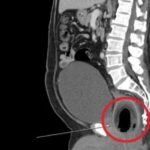

O apresentador Paulo Mathias, do SBT, passou por um susto enquanto comandava o Chega Mais. O comunicador convidou o médico Antonio Rahal para falar sobre câncer e realizou um ultrassom ao vivo para demonstrar a facilidade de um exame de para a prevenção da doença.

Entretanto, o que o jornalista não contava, era que o profissional encontraria um cisto em sua tireoide. “Eu achei aqui um ‘nodulozinho’ nele, fica tranquilo, Paulo”, disse que o médico. “O que o senhor tá falando? Eu tô em pânico”, se espantou o jornalista.

Rahal explicou, entretanto, que se tratava de um nódulo pequeno e misto, sólido e cístico, com classificação T-RADS 3. Apesar do susto, ele relatou que a chance de que seja maligno é menor que 5%.